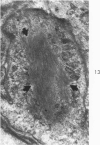

Liver biopsies obtained from 24 patients with alcoholic liver disease were studied by light and electron microscopy. Comparisons of the same cells in adjacent sections revealed that alcoholic hyalin is a fibrillar deposit without limiting membranes and is readily distinguished from giant mitochondria. This characteristic fibrillar structure was encountered in hepatocytes, ductular cells and in benign and malignant hepatomas. Three distinct morphologic forms of alcoholic hyalin were observed: a) bundles of filaments in parallel arrays, b) clusters of randomly oriented fibrils and c) a granular or amorphous substance containing only scattered remains of fibrils. Closely associated with alcoholic hyalin and often found along its entire circumference, were bundles of fine filaments in parallel arrangement of much smaller size. These occasionally displayed variations in orientation and merged with the filaments in the alcoholic hyalin body. Similar fine filaments were observed, in considerable excess, in cells which did not contain alcoholic hyalin. According to our findings, the fine filaments and the significantly larger filaments in alcoholic hyalin could be parts of a contractile system elaborated by host cells during the course of hepatic injury.